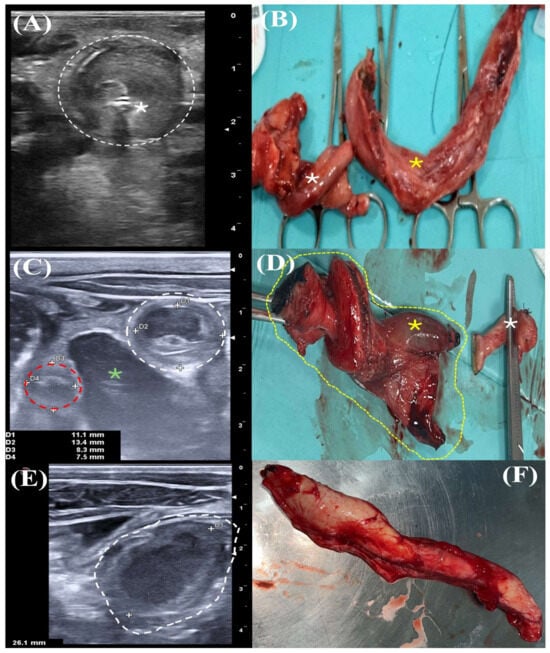

3.1.1. Clinical Case 1

3.1.2. Clinical Case 2

3.1.3. Clinical Case 3

3.1.4. Clinical Case 4

3.1.5. Clinical Case 5